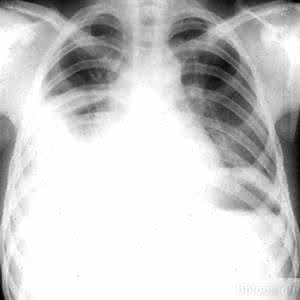

大多数结核性胸膜炎是急性病。其症状主要表现为结核的全身中毒症状和胸腔积液所致的局部症状。

结核中毒症状主要表现为发热、畏寒、出汗、乏力、食欲不振、盗汗。局部症状有胸痛、干咳和呼吸困难。胸痛多位于胸廓呼吸运动幅度最大的腋前线或腋后线下方,呈锐痛,随深呼吸或咳嗽而加重。

由于胸腔内积液逐渐增多,几天后胸痛逐渐减轻或消失。积液对胸膜的刺激可引起反射性干咳,体位转动时更为明显。

积液量少时仅有胸闷、气促,大量积液压迫肺、心和纵隔,则可发生呼吸困难。积液产生和聚集越快、越多,呼吸困难越明显,甚至可有端坐呼吸和发绀。